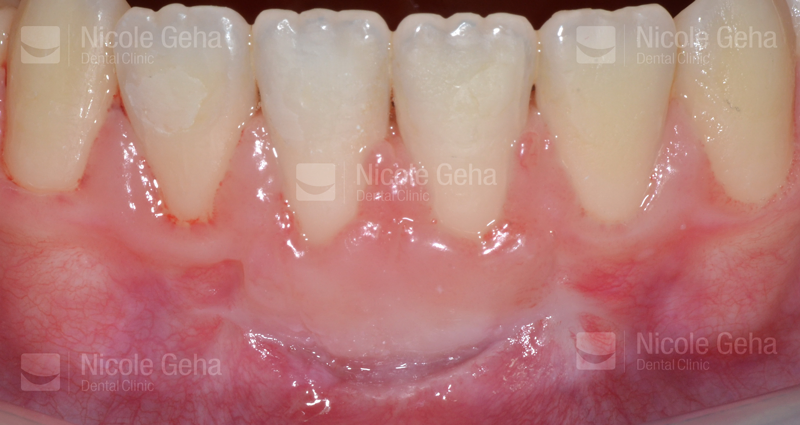

MULTIPLE IMPLANTS

case 1: Before Extraction

case 1: after